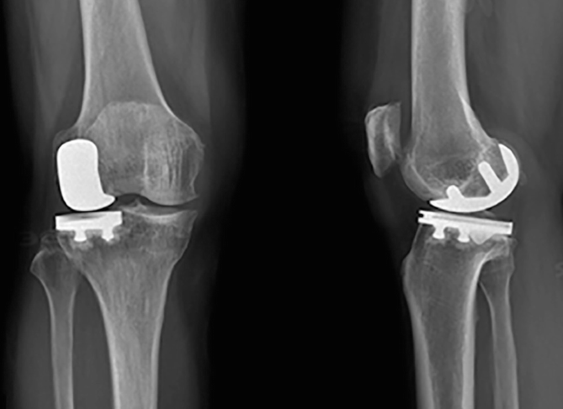

• Prothèse partielle / unicompartimentaire : Elle remplace uniquement la partie usée du genou.

• Prothèse totale : Elle remplace toute l’articulation du genou.